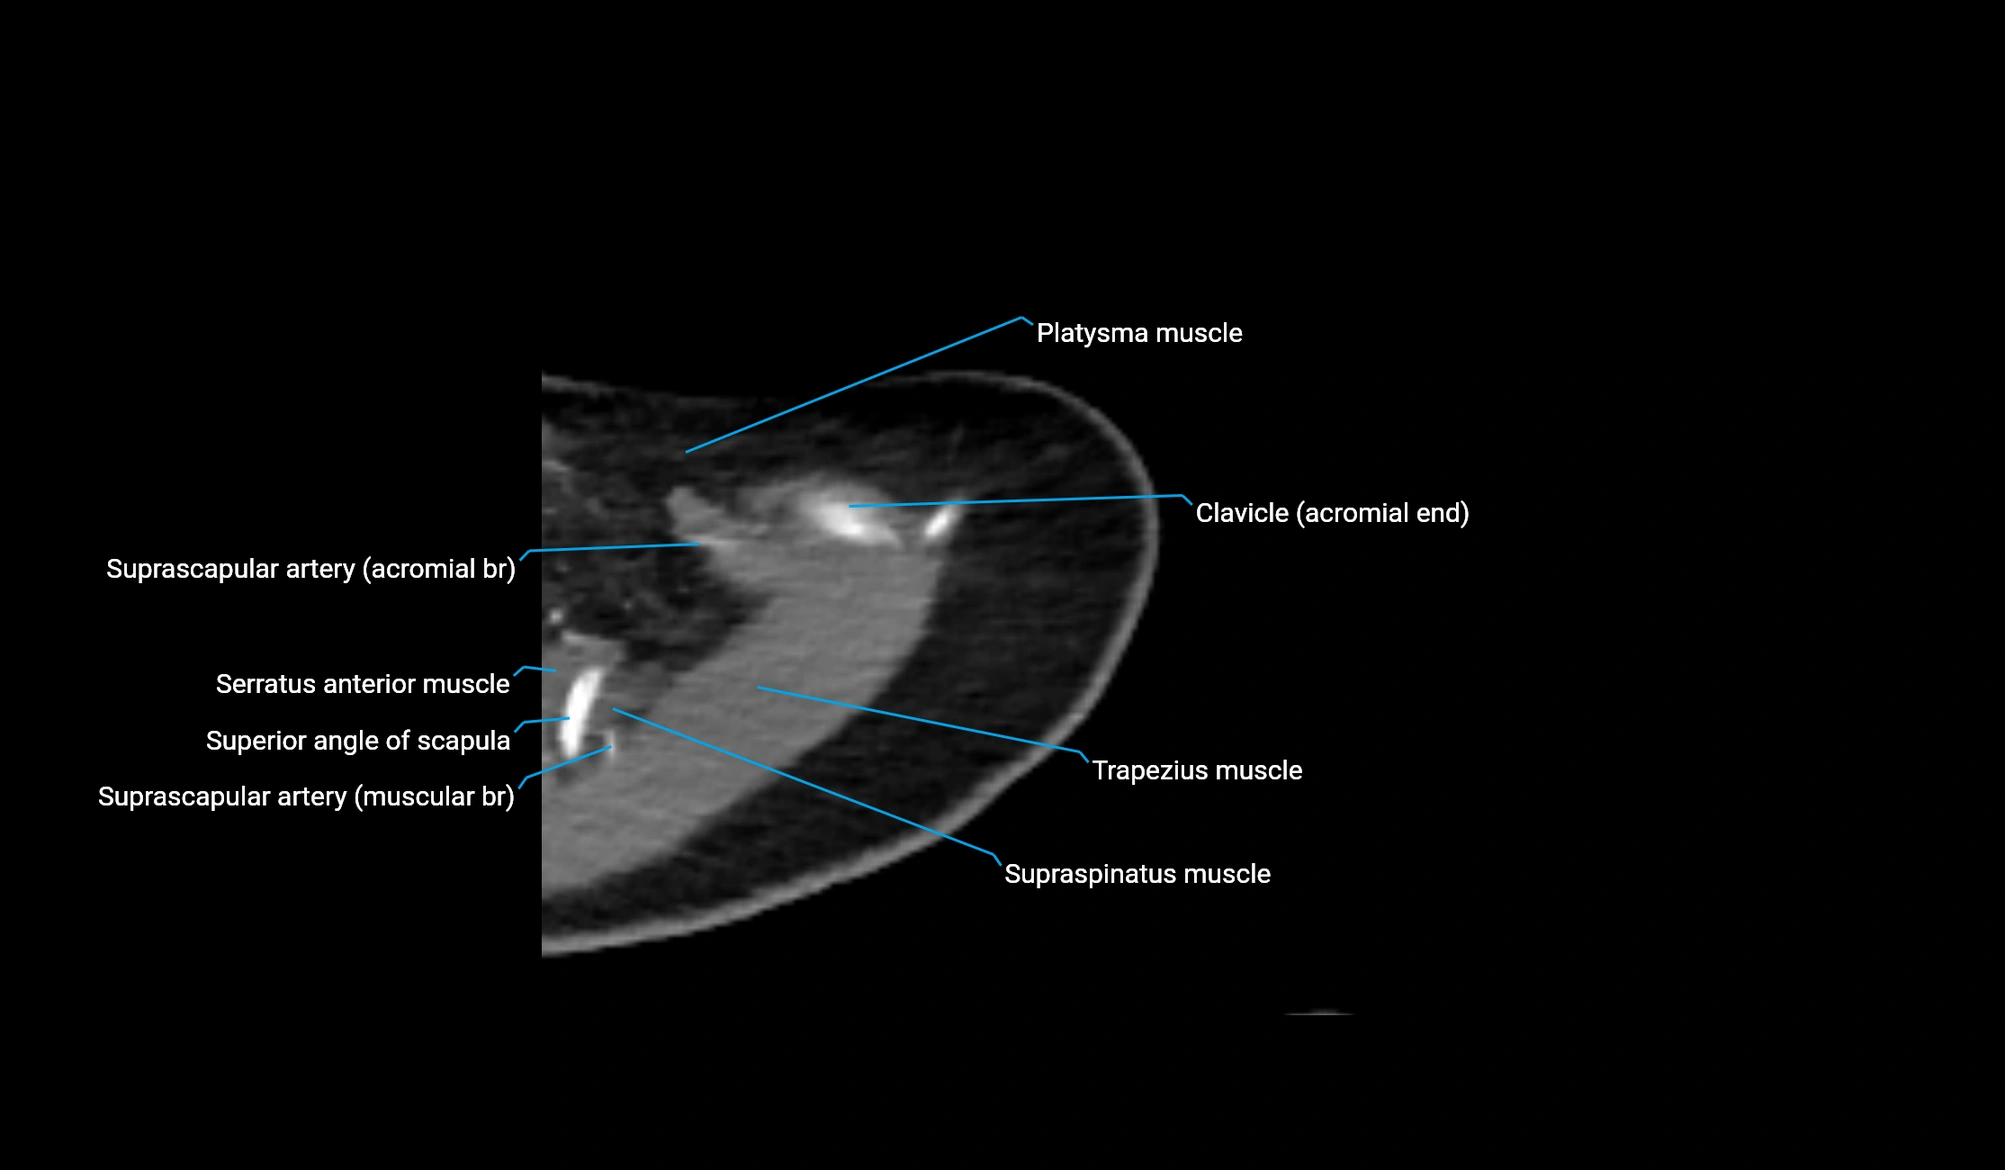

CT image